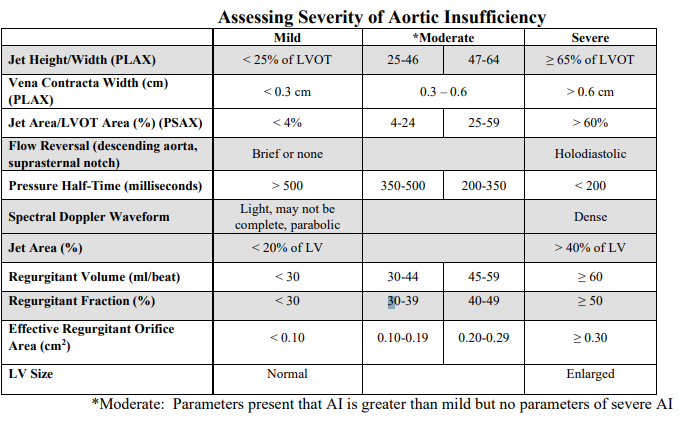

Mild AI

Jet height/width

vena contracta

PHT

Spectral doppler waveform

flow reversal

jet area

regurgitant oriface area

LV size

• Jet height/width (LVOT) <25%

• Vena contracta width less than 0.3 centimeters

• Pressure half-time greater than 500 milliseconds

• Light or incomplete density of the spectral Doppler waveform

• Only brief or no diastolic flow reversal in the descending aorta

• Jet area less than 20% of the left ventricle

• Regurgitant orifice area less than 0.10 cm2

• Normal left ventricular size

Severe AI

Jet height/width

vena contracta

PHT

Spectral doppler waveform

flow reversal

jet area

regurgitant oriface area

LV size

• Jet height/width (LVOT) ≥ 65%

• Vena contracta width greater than 0.6 centimeters

• Pressure half-time less than 200 milliseconds

• Holodiastolic flow reversal is seen in the descending aorta (supraternal window)

• Jet area greater than 40% of the left ventricle

• Regurgitant orifice area ≥ 0.30 cm2

• Dense spectral Doppler signal

• Left ventricular enlargement

AI PHT

mild

moderate

moderatley severe

severe

jet height (PLAX)

mild

moderate

moderatley severe

severe

Jet height / LVOT Height (PLAX)

mild

moderate

moderatley severe

severe

Jet area / LVOT area (PSAX)

mild

moderate

moderatley severe

severe

Vena contracta width (cm) (PLAX)

mild

moderate

severe

mild

< 0.3 cm

moderate

0.3 - 0.6 cm

severe

> 0.6 cm

Jet area / LVOT area (%) (PSAX)

mild

moderate

severe

mild

<4%

moderate

4 - 24%

25 - 59%

severe

>60%

Flow reversal (descending aorta, suprasternal notch)

mild

moderate

severe

mild

brief or none

moderate

severe

holodiastolic

AO PHT (ms)

mild

moderate

severe

mild

>500 ms

moderate

500 - 350 ms

350 - 200 ms

severe

< 200 ms

Spectral doppler waveform

mild

moderate

severe

mild

Light, may not be complete, parabolic

moderate

severe

Dense

AI Jet area

mild

moderate

severe

mild

< 20% of LV

moderate

severe

> 40% of LV

Regurgitation volume (mL/beat)

mild

moderate

severe

mild

<30 mL/beat

moderate

30 - 44 mL/beat

45 - 59 mL/beat

severe

≥ 60 mL/beat

Regurgitaion fraction (%)

mild

moderate

severe

mild

< 30%

moderate

30 - 39%

40 - 49%

severe

≥ 50%

Effective Regurgitant oriface area (cm²)

mild

moderate

severe

mild

< 0.10 cm²

moderate

0.10 - 0.19 cm²

0.20 - 0.29 cm²

severe

≥ 0.30 cm²

LV Size

mild

moderate

severe

mild

normal

moderate

severe

Enlarged